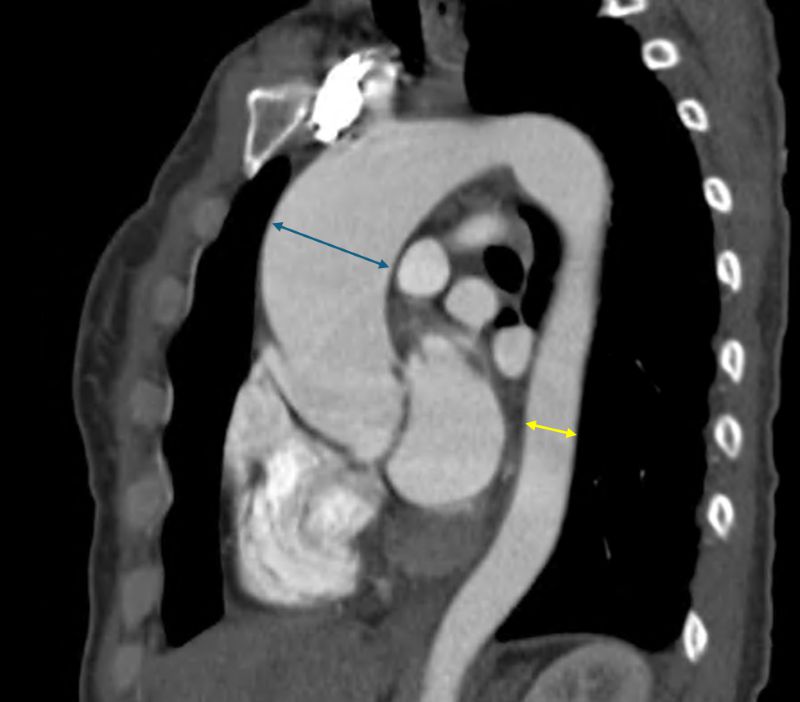

48歲陳女士,6個月前就出現活動時胸悶、喘不過氣的症狀,甚至數度因接近昏倒被送醫,但她一直未將不適放在心上。直到今年3月,她因不適至鄰近醫院檢查心臟超音波,才發現罹患重度主動脈瓣膜狹窄,隨時可能導致猝死,因此緊急轉診至台北慈濟醫院治療。心臟血管外科楊凱文醫師替其以心導管與電腦斷層進行術前評估,發現她不僅主動脈瓣膜鈣化嚴重,主動脈也已有近5公分的動脈瘤,未來可能有破裂風險,此外,她的主動脈瓣更是天生只有兩片(正常為三片)。在與病患討論後,楊醫師採用微創僅6公分的開胸方式,更換人工主動脈瓣膜與人工血管,減少出血疼痛,術後一天,陳女士即轉入普通病房,加速術後復原。

主動脈瓣由三片瓣葉構成,心臟收縮時開啟,放鬆時閉合,防止血液回流。若瓣膜退化因肥厚、鈣化無法正常開合,因此影響全身血流血流,即為「主動脈瓣狹窄」。一般而言,重度主動脈瓣膜狹窄多見於70歲以上病人,而年輕如陳女士般尚未50歲就發生嚴重鈣化與狹窄的多是先天性雙瓣的主動脈瓣者。楊凱文醫師指出,先天性雙瓣主動脈瓣膜的患者在中年即容易出現瓣膜狹窄或閉鎖不全,並伴隨主動脈擴大的問題。國外統計指出,約有40-60%的雙瓣主動脈瓣患者會出現主動脈瘤或主動脈擴大情形。

楊凱文醫師指出,重度主動脈瓣膜狹窄的病人,唯一治療方式就是開刀置換主動脈瓣,無法僅靠藥物控制。目前的手術方式有開心手術與經鼠蹊部導管置換主動脈瓣手術兩種,由於病人合併有主動脈瘤且不符合後者的健保適應症,醫療團隊以開心手術的方式替其治療。特別的是,傳統開心手術需劈開整塊胸骨,傷口可達15至20公分,但楊凱文醫師採J型鋸開胸骨,以僅約6公分的傷口,將已經鈣化的瓣膜組織完整切除,接著處理主動脈內部殘留的鈣化區塊,進行去鈣化和壓碎處理。之後,植入一枚新的人工生物瓣膜。同時,將動脈瘤的部分一併切除,再以手縫方式接上人工血管,完成修復。由於陳女士不希望長期服用抗凝血藥物,因此選擇植入新一代的生物瓣膜,雖然生物瓣膜僅有約10至15年的壽命,但未來若瓣膜退化,可透過微創導管手術直接置換新瓣膜,無需再次開胸,大幅降低風險。